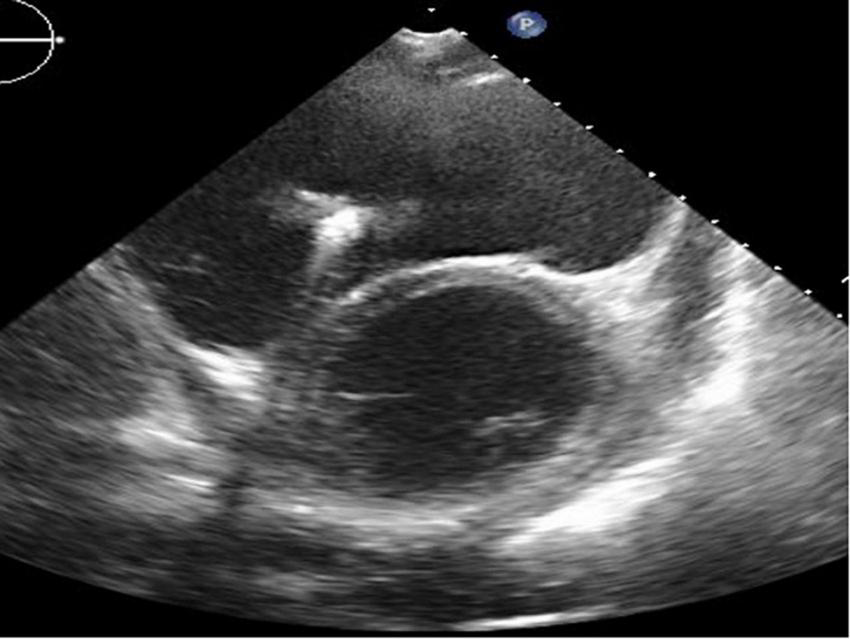

FIGURE 5

Long-axis view at end-diastolic phase of transthoracic echocardiography in Case 3. Note that the right ventricle is much larger than the left ventricle, and the left ventricle is very small (end-diastolic dimension 31 mm).